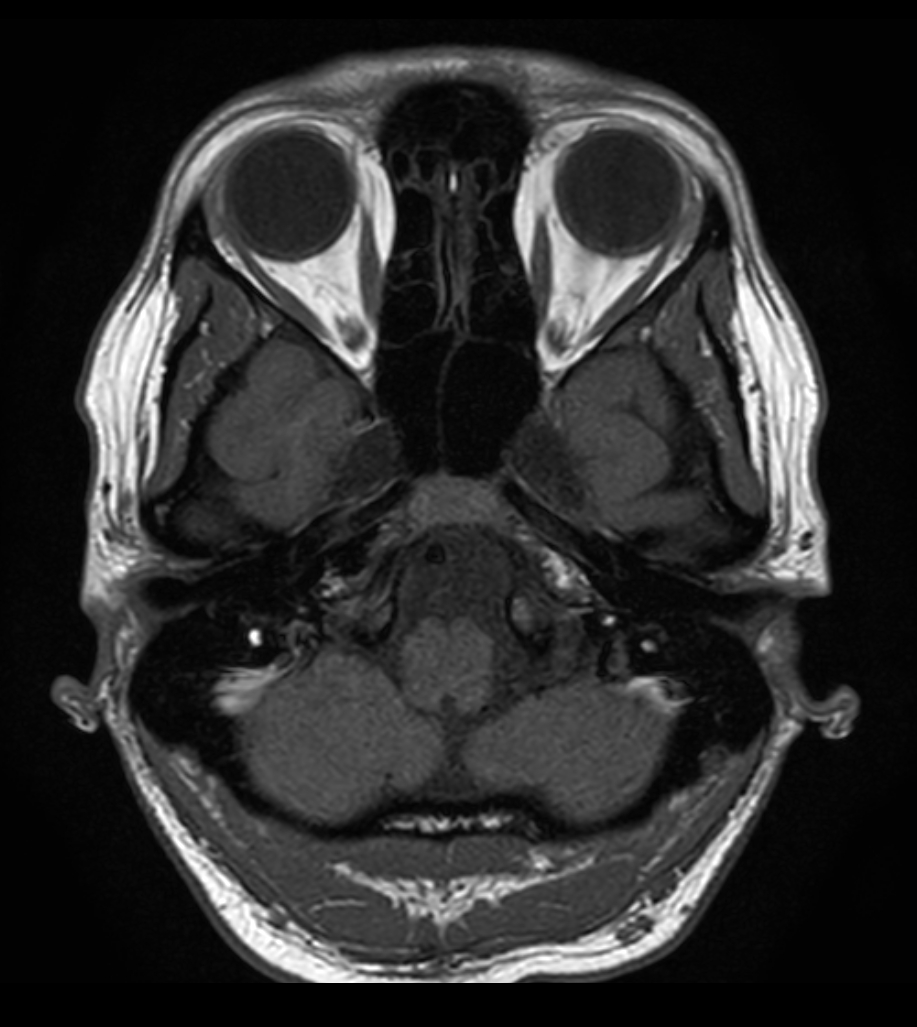

DWI (b1000)